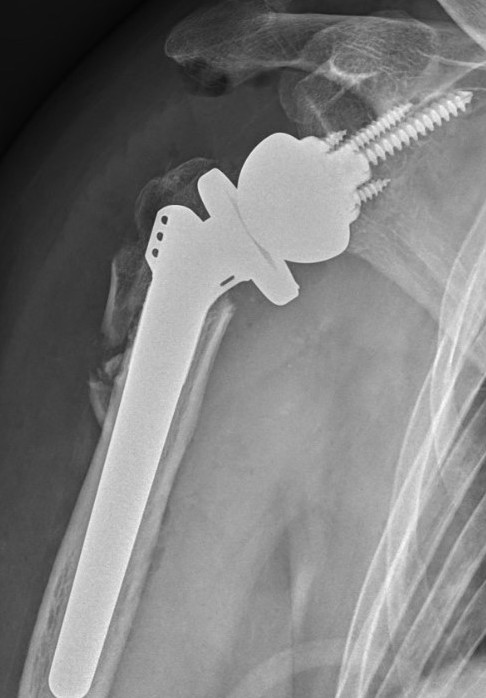

Arthroplasty

Indications

RA

- very good results

- 97% 10 year survival Coonrad-Morrey prosthesis

Other Dx

- OA / post-traumatic arthritis / nonunion

- tend to have worse survival than RA